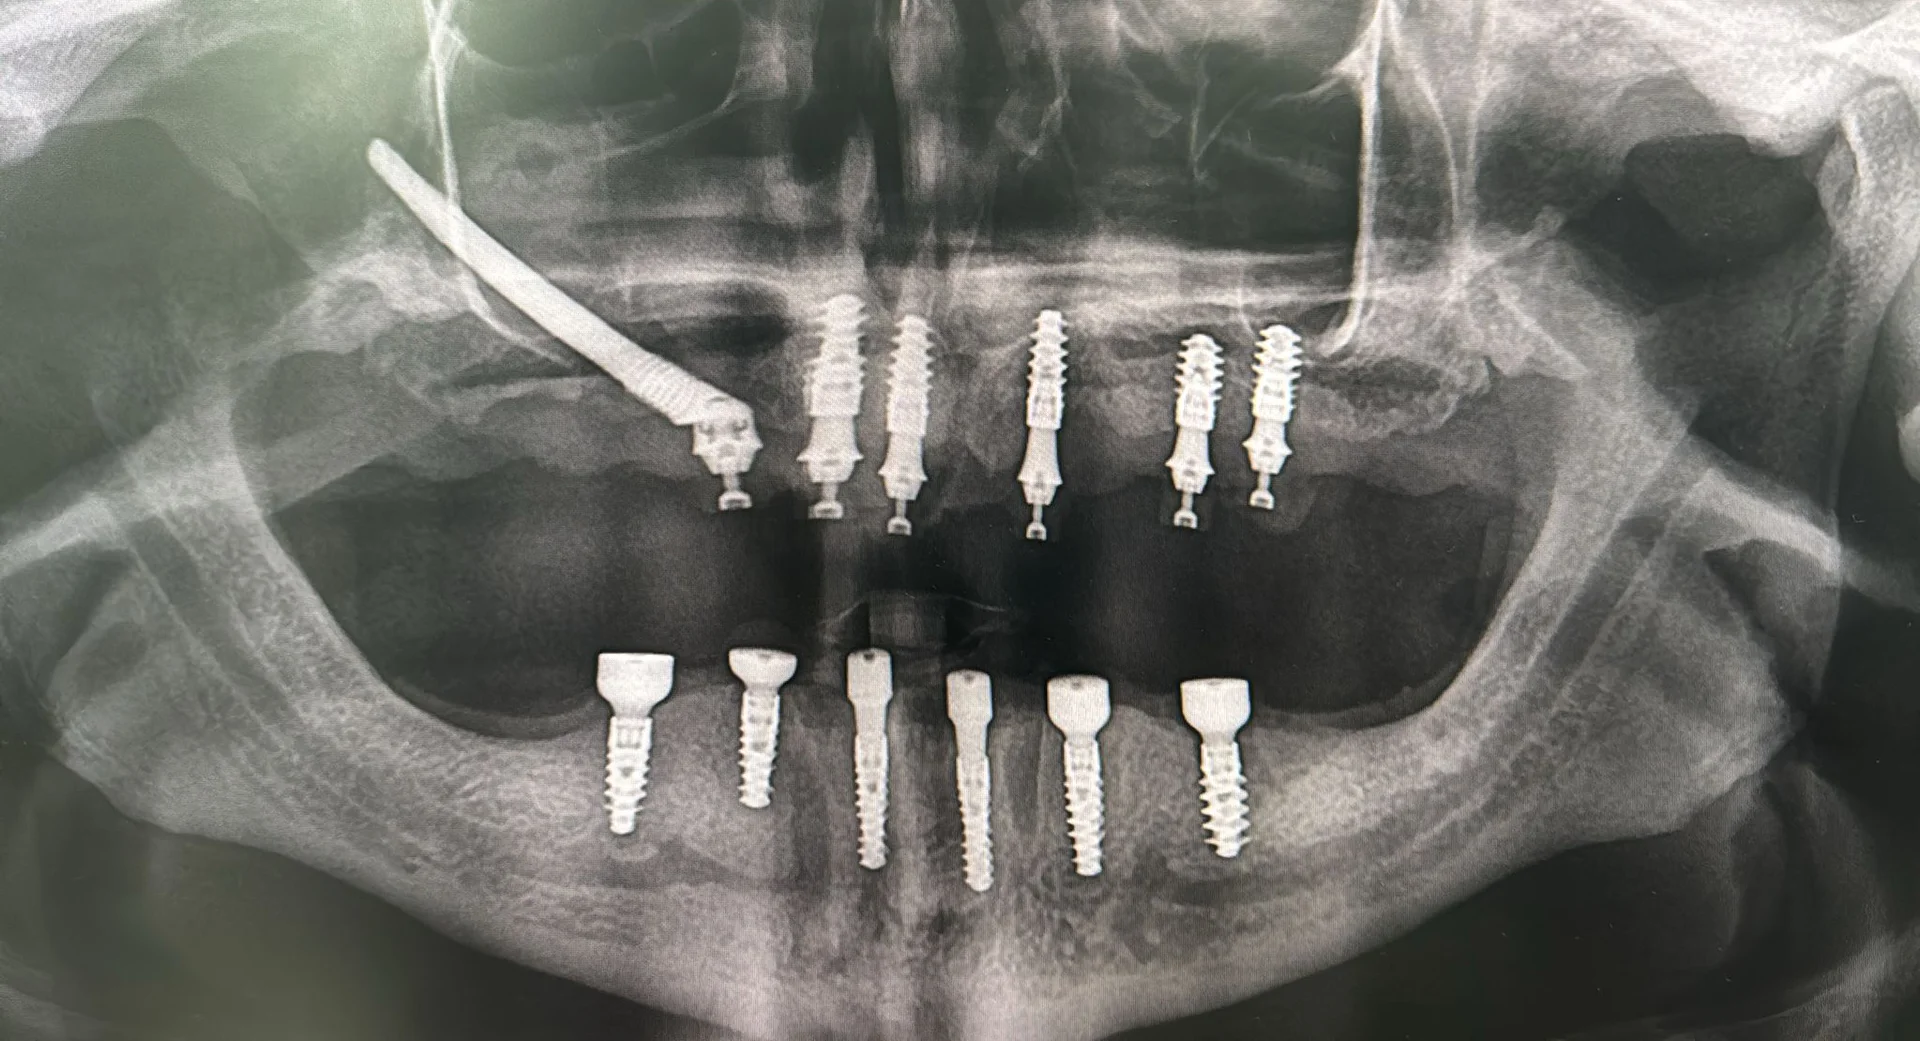

Zygomatic dental implants are specially designed for people who have severe bone loss in the upper jaw. Unlike regular implants that go into the jawbone, these implants are anchored in the cheekbone (zygomatic bone).

The cheekbone is much denser and stronger than the jawbone, so it provides a solid base for implants even when the jawbone has weakened. This method allows you to get fixed teeth without needing bone grafts or sinus lift surgery.

How Many Zygomatic Implants Are Needed?

The number of zygomatic implants depends on your bone structure and how many teeth you’re missing.

- In some cases, just two zygomatic implants plus traditional implants are enough.

- In more advanced cases, four zygomatic implants may be used.

- Sometimes, a full set of upper teeth can be supported with only four zygomatic implants.

We determine the best option after a full clinical evaluation and 3D scan.